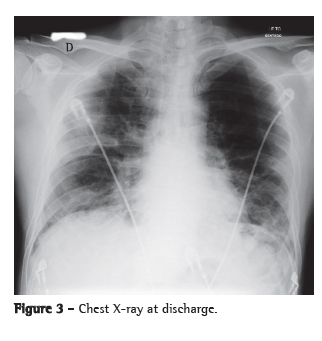

The patient was admitted to the ICU and treated with oseltamivir, ceftriaxone, azithromycin and a corticosteroid. He received ventilatory support with intermittent positive pressure breathing, which was maintained at 50% via a Venturi mask, at a resting SpO2 of 92%. The patient progressively improved and was discharged from the ICU ten days later, presenting an SpO2 of 94% on room air, together with radiological improvement (Figure 3). He developed no fever or hemodynamic instability during the hospital stay.